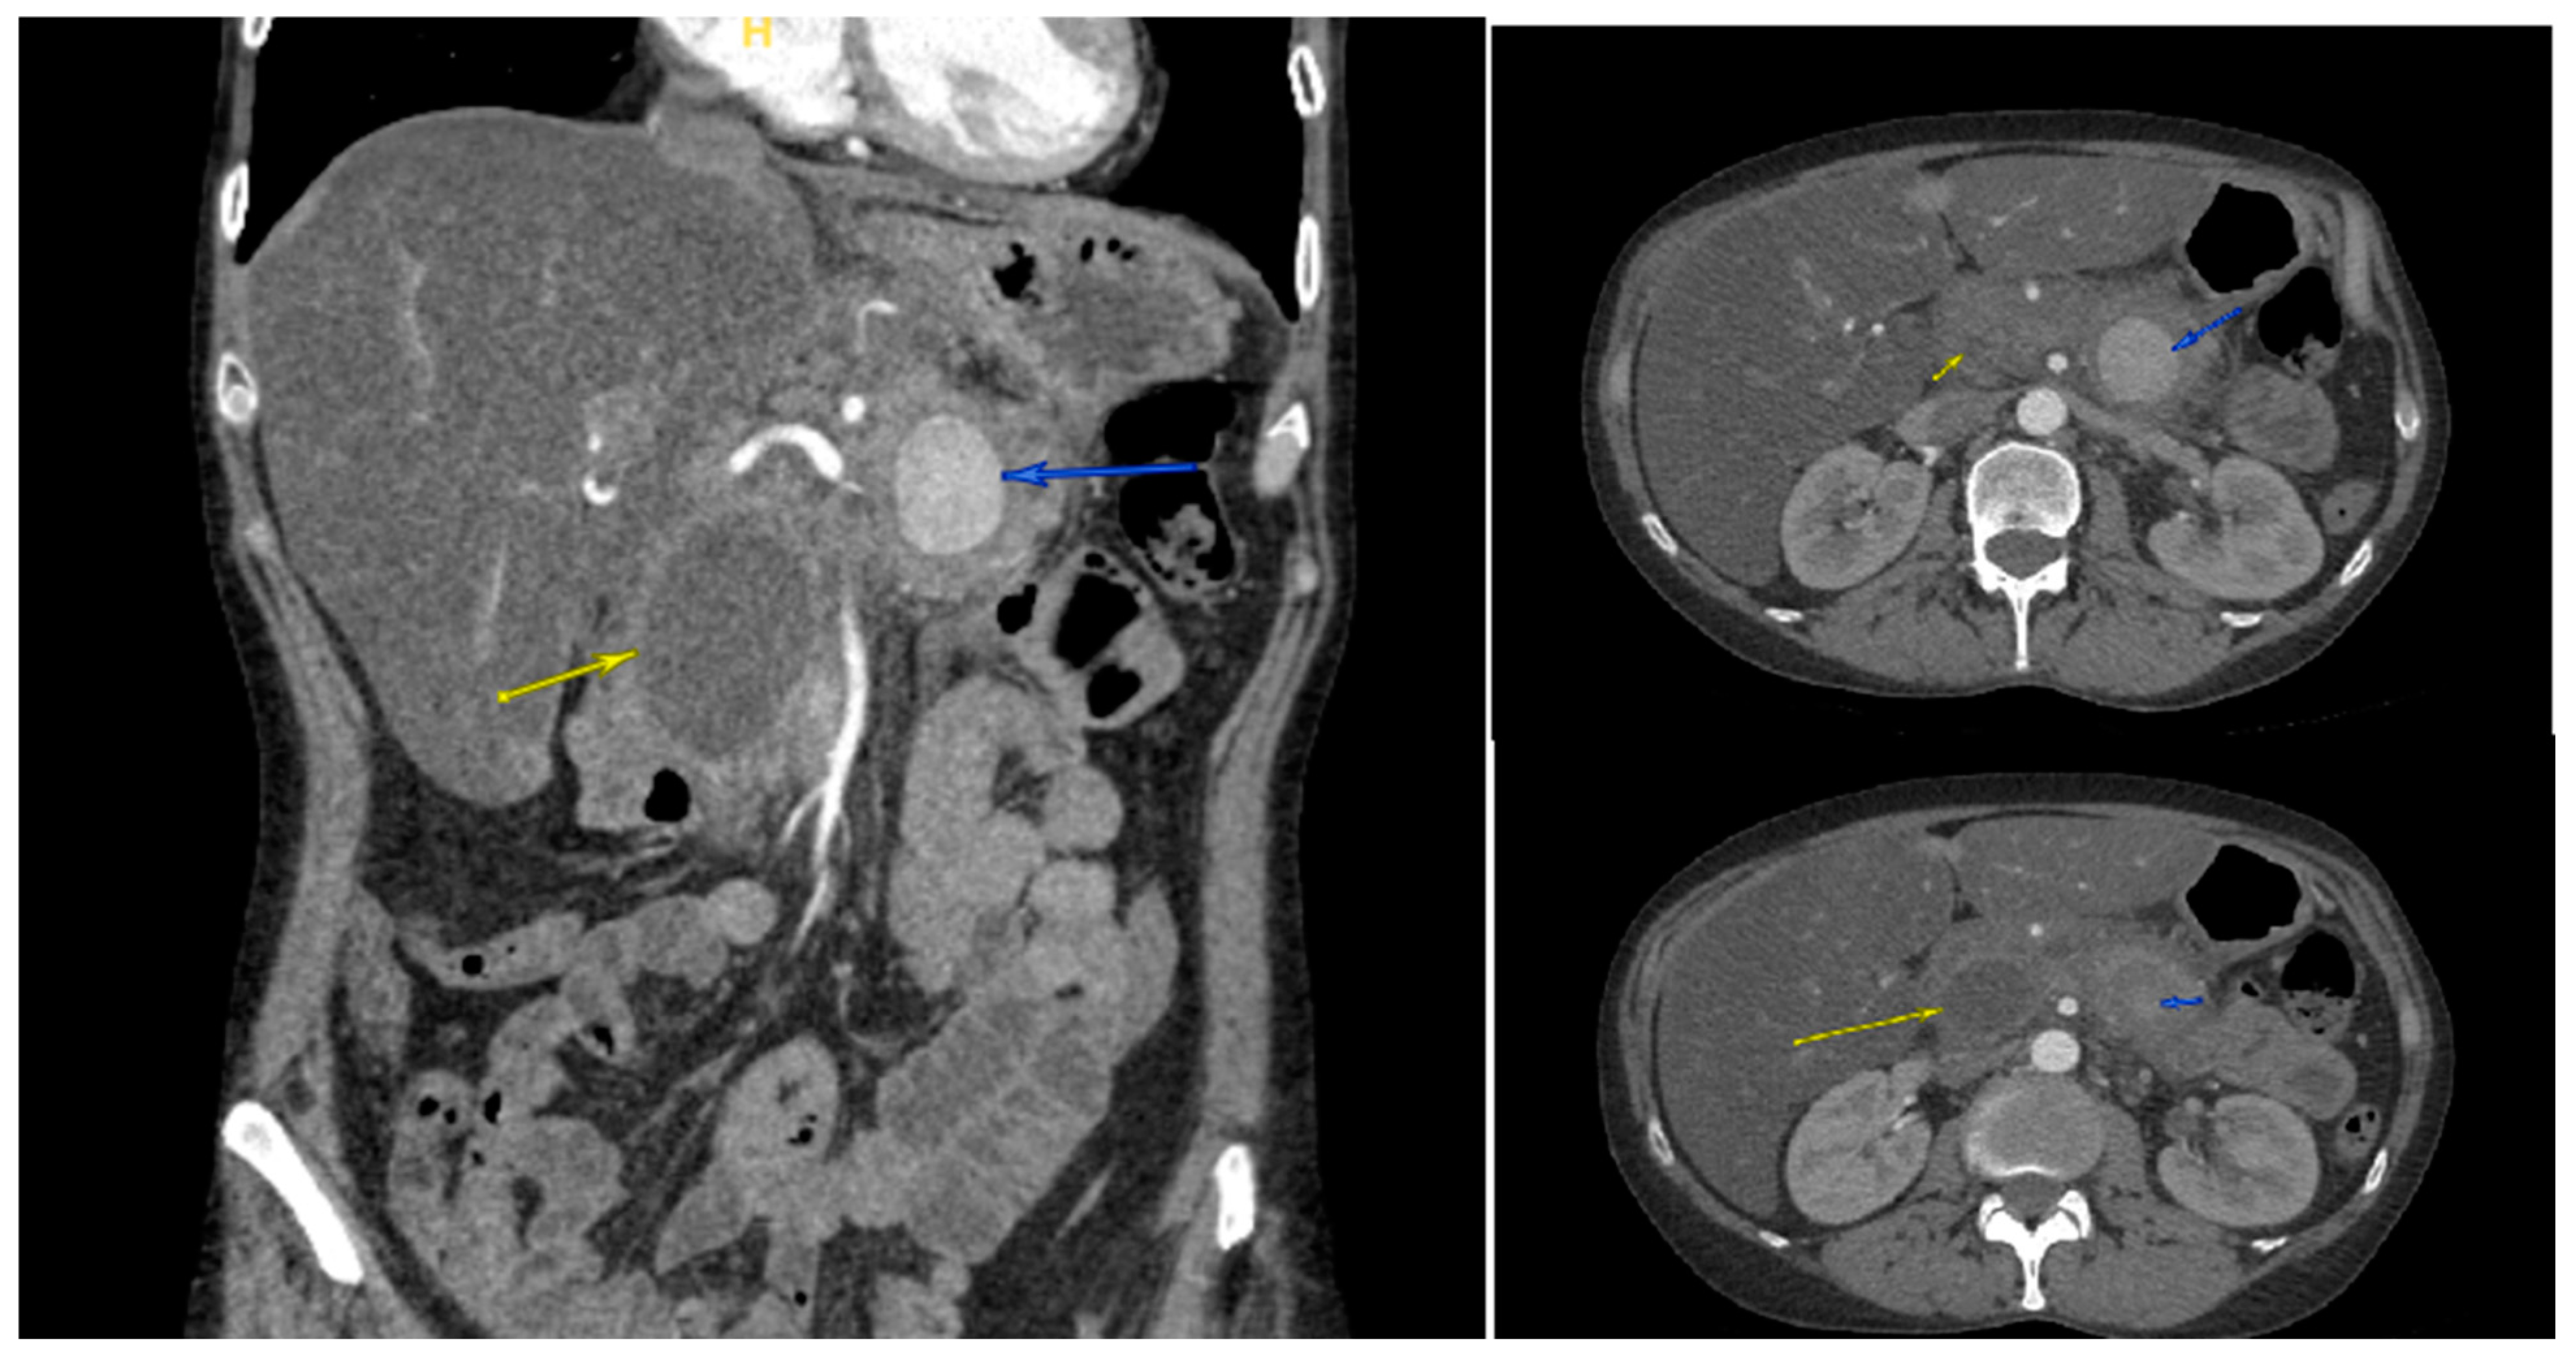

2. Case Presentation